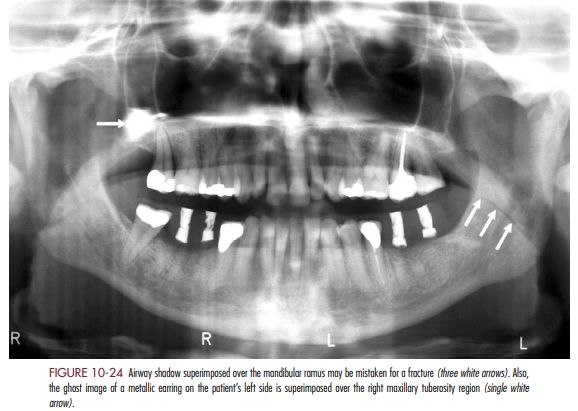

65.圖中箭頭所指之放射線透過性線條(radiolucent line)為下列何者在下顎上升枝的重疊影像?

(C)口腔氣道(oral airway)

其他landmark 也看一下